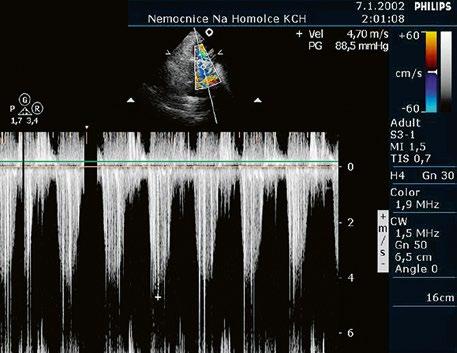

Malé restriktivní defekty komorového septa (Rogerova choroba) nevedou ke vzniku plicní hypertenze ani k srdečnímu selhání. Mají typickou vysokorychlostní dopplerovskou křivku (Obr. 45.35), odpovídající vysokém gradientu mezi levou a pravou komorou v systole a poslechovému nálezu hlučného systolického šelestu.

Obr. 45.35 CW záznam vysokorychlostního dopple rovského toku z levé do pravé komory malým restriktivním defektem komorového septa. Vysoký gradient na komorovém defektu vylučuje vysoký tlak v pravé komoře při plicní hypertenzi nebo při těžké stenóze plicnice.

z mírná: Vmax do 3 m/s, max. grad. 36 mmHg; z střední: Vmax 3–4 m/s, max. grad. 36–64 mmHg; z těžká: Vmax nad 4 m/s, max. grad. nad 64 mmHg.

Obr. 45.45 Těžká, dlouhodobě neřešená valvární a subvalvární stenóza plicnice s vysokým gradientem 155/82 mmHg (CW doppler) (viz též Obr. 45.44)